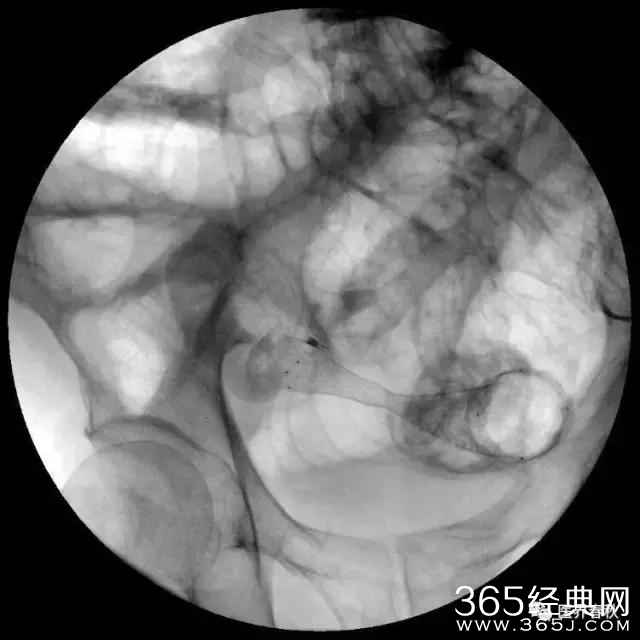

高难度狭窄处U型弯结肠支架植入术

支架成功释放后